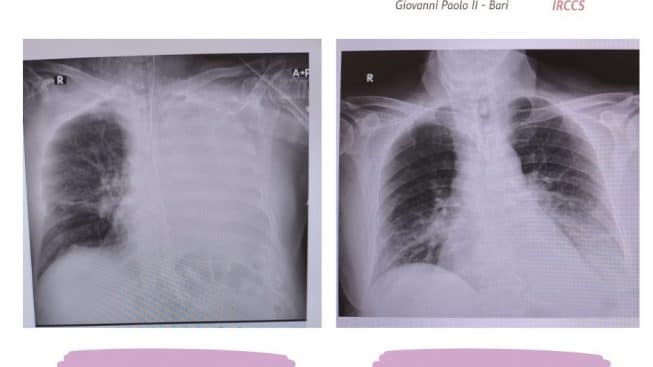

Intervento palliativo salvavita per un paziente di 63 anni affetto da microcitoma polmonare metastatico all’Istituto Tumori Giovanni Paolo II di Bari: il paziente, arrivato da un ospedale tarantino, presentava una occlusione completa neoplastica del bronco principale sinistro. In buona sostanza, il tumore gli comprimeva completamente la trachea, impedendogli di respirare. Così il dottor Gaetano Napoli, direttore dell’unità operativa di Chirurgia Toracica Mininvasiva, gli ha impiantato una protesi autoespandibile in nitinol (una speciale lega di nichel e titanio con una percentuale più o meno uguale dei due elementi) nel bronco principale sinistro (in cui riusciva a passare appena la guida per la procedura di dilatazione), riuscendo così a disostruirlo.

Ora il 63enne è tornato a casa e, con questo intervento salvavita, potrà cominciare il trattamento radio-chemioterapico per la cura del tumore.